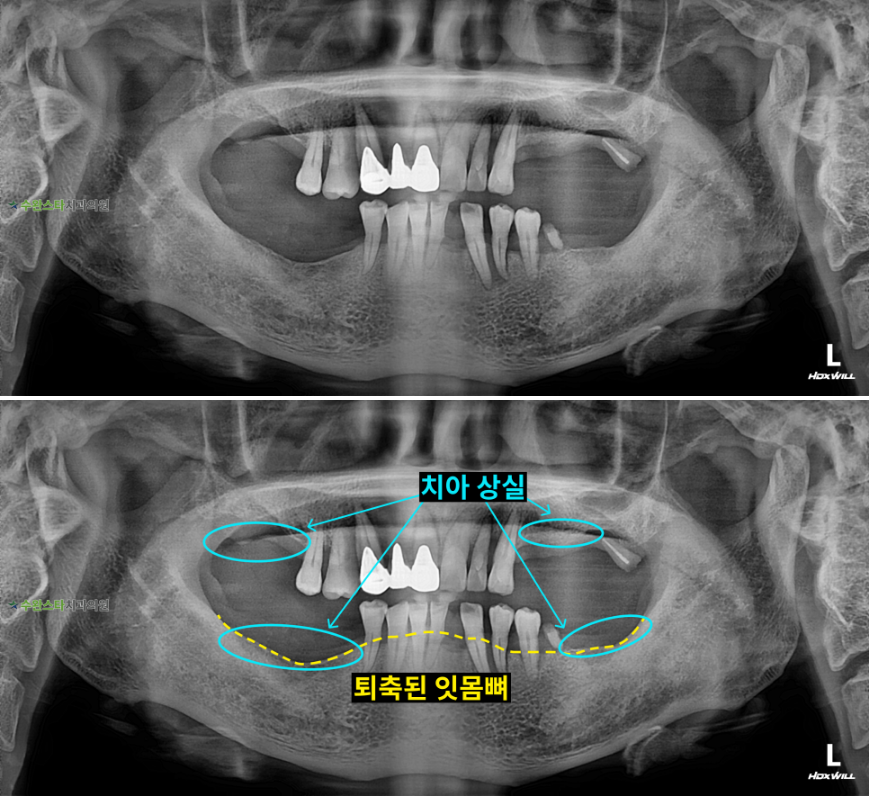

내원 시 파노라마

처음 내원 시 파노라마, 50대 남성 (2025.8 촬영)

내원 시 파노라마 사진입니다.

어금니가 전체적으로 상실되어

식사가 어려우셨다고 합니다.

잇몸뼈가 많이 녹은 경우

자연치아를 살릴 수 없어

발치 후 뼈 이식과 임플란트가

필요합니다.